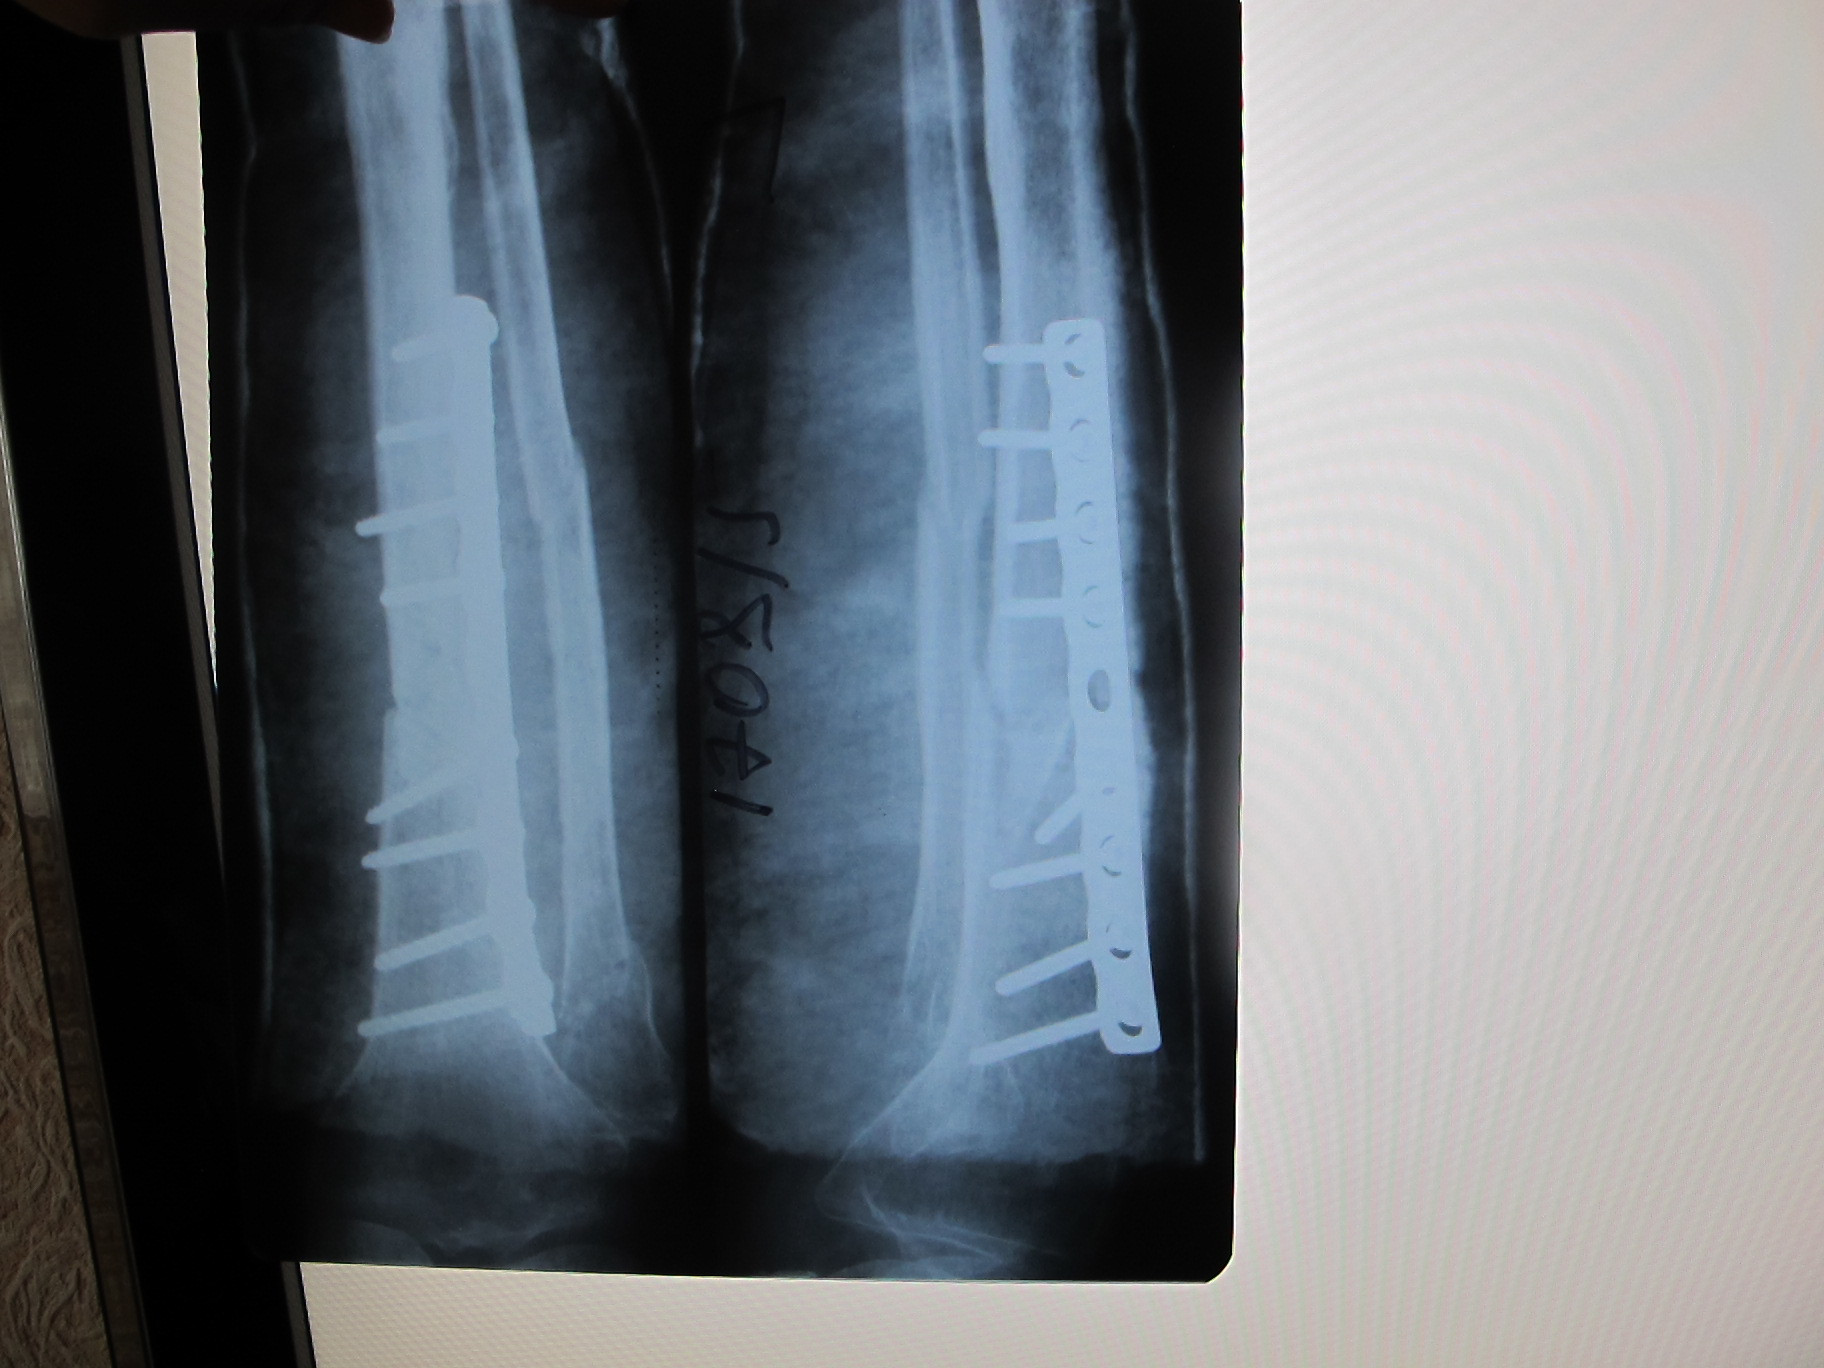

Вот такая конструкция теперь красовалась в моей ноге) В этот же день хирург пришел на осмотр, сказал, что можно вставать на костыли и давать нагрузку ноге до 20 кг. Плюс было назначено физиолечение (магнит), лечебная гимнастика.

Здравствуйте меня зовут Валентина мне 31 год. 21 августа сломала ногу 5 дней на вытяжке 26 августа операция "Биос".У меня перелом малой и большой берцовой кости в нежней третей части. После операции наложили гипсовый лангет,носила 1,5 месяца.Сделали снимое перелом сросся плохо. Большая берцовая кость была зафиксированна шурупами и спицой и она немного срослась,а малая берцовая нет т.к. должна была зафиксироваться от большой кости. Подскажите сколько носить гипсовый лангет и почему не срослась малая кость и какие будут последствия если малая так плохо сростается.

А вы в такие малые сроки ничего и не увидите! Перелом голени в самых хороших случаях срастается за 3,5-4 месяца. Можете посмотреть мои снимки (пост выше), там даты есть. Я тоже задавал врачам вопросы по поводу малоберцовой кости, мне сказали не беспокоиться, всё срастется. хотя меня тоже гложут сомнения по этому поводу. А снимки у вас есть? Костная мозоль при пульпации прощупывается?